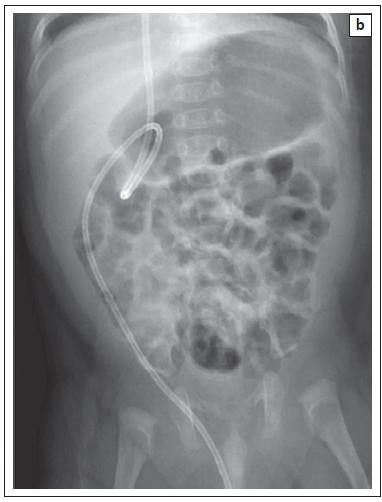

Shunts can be improperly positioned at the level of the ventricles or within the peritoneum (Figure 12a and Figure 12b); similarly, shunt migration can occur at both ends. Within the abdomen, the viscera can also be perforated by the shunt.